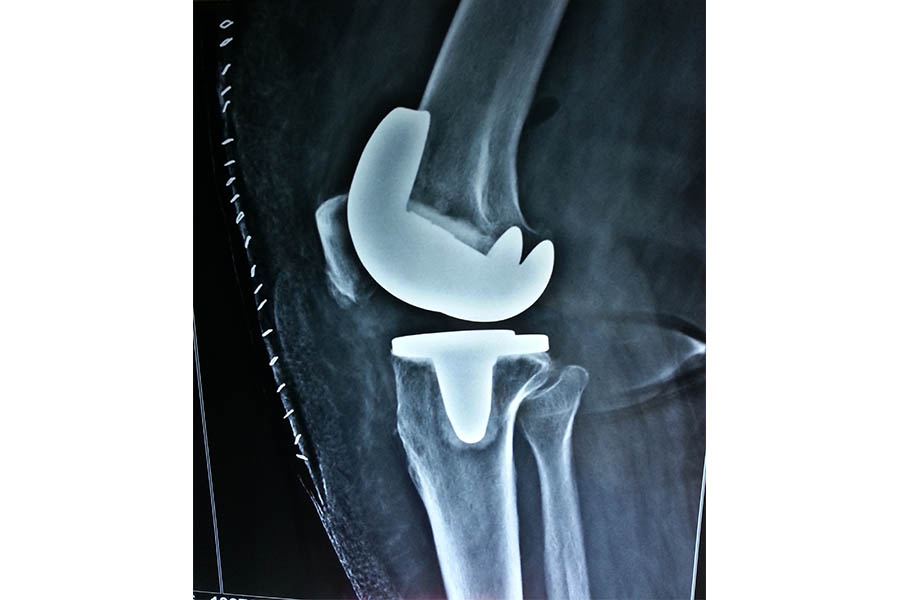

Total Elbow Replacement

Case 1